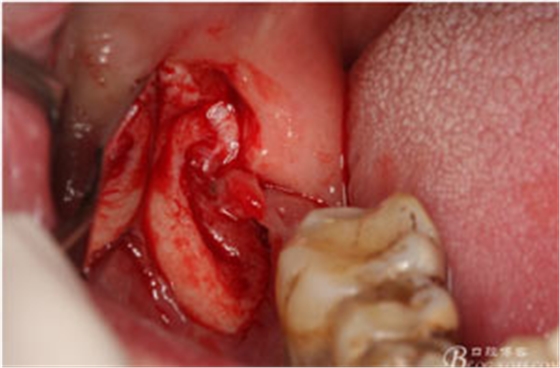

圖6.行角形瓣切開、翻瓣、暴露骨面,可見48牙冠表面有炎性肉芽組織